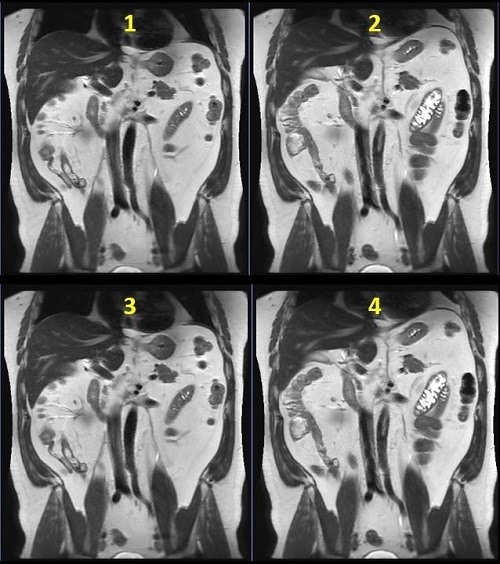

Figure 5. Abdomen comparison images

Table 5. Image legend Number Description 1 Breath Hold: 32 seconds 2 3 locations per trigger: 1:12 3 2 locations per trigger: 1:48 4 1 location per trigger: 3:35 - For multi-slice SSFSE with Navigator Imaging Option scans, click the Run RR Measurement option button. This ensures that the respiratory rate can be calculated at download, and the number of locations per trigger updated accordingly.